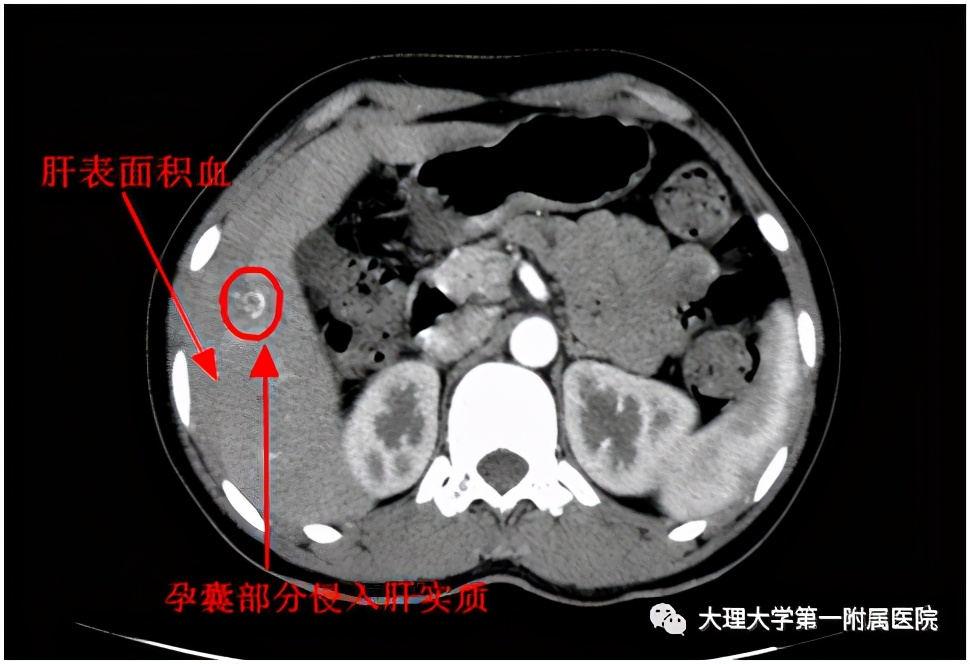

12月3日,在家人的陪伴下,她来到了大理大学第一附属医院普外一科门诊,找到石洪波副主任医师就诊。石医生详细了解了阿女士的病情后,立刻将其收住至普外一科住院,并开通绿色通道让她做全面检查,准备手术。石医生在查看检查结果发现:阿女士的右肝上的肿瘤的确已经破裂出血,同时她的怀孕指标(β-HCG)高达2000IU/L!

看完有明显怀孕指征的报告单后,石医生再次询问了阿女士的月经周期,原来连阿女士自己都不知道自己是否怀孕。为了制定全面的治疗方案,石医生安排阿女士又进一步做了妇科B超检查,可检查结果却让人匪夷所思——没有在其子宫内发现孕囊。

右肝上的小肿瘤是什么?超高的怀孕指标系数明显表明阿女士已经怀孕了,但为什么没有在子宫内找到孕囊呢?

为了消除疑虑,普外一科主任谭云波教授和石洪波副主任立刻组织全科讨论并仔细分析后,大家高度怀疑阿女士右肝上已经出现破裂出血的小肿瘤就是孕囊。此时,阿女士已经失血500ml左右了,如果不尽快为其止血,她随时会发生因失血过多再次造成休克。经过大家对阿女士进行全面评估,决定为其施行手术。